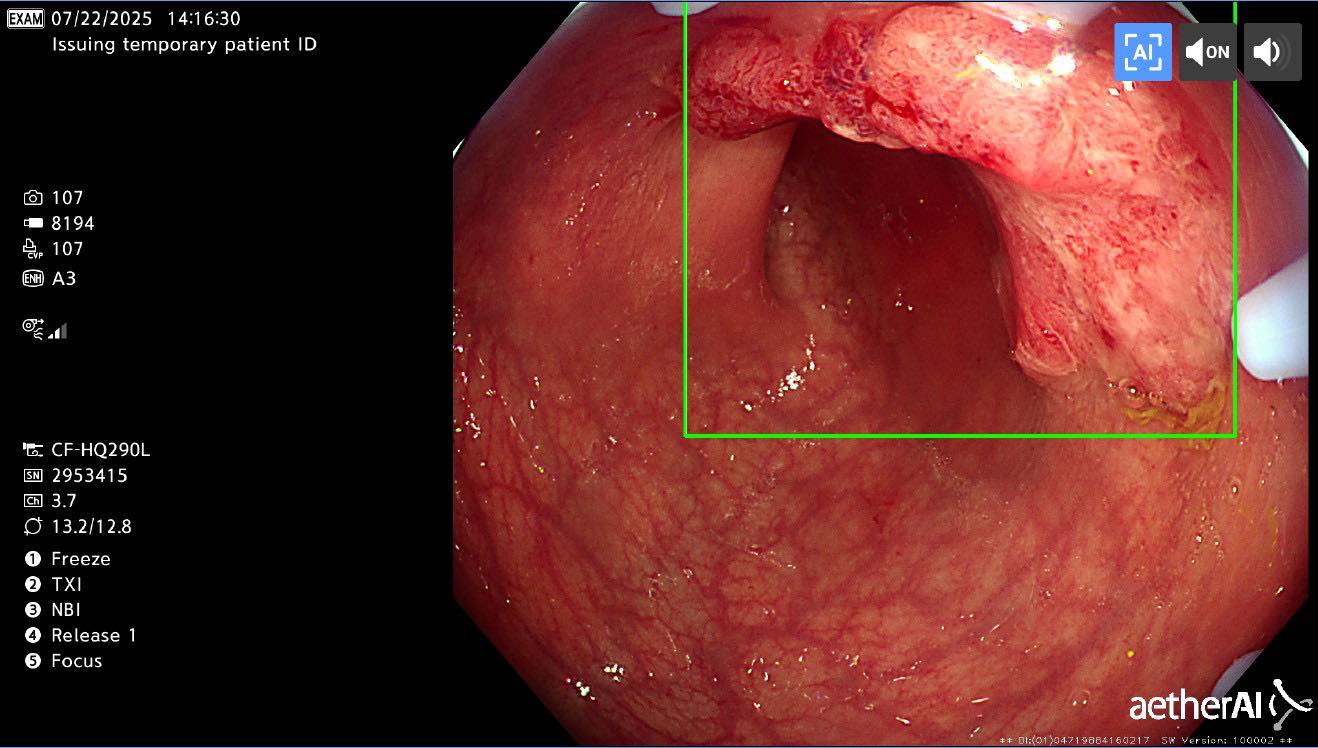

前幾天,我替一位只有 28 歲的病人做大腸鏡

前幾天,我替一位只有 28 歲的病人做大腸鏡,他原本只是順便檢查,事前沒有任何症狀,結果居然確診是大腸癌。當我告訴他時,他沉默了很久,眼神裡除了震驚,還有一種「怎麼可能是我」的無助,那份沉重,讓人真的喘不過氣。

很多人覺得大腸癌是五、六十歲以後才會遇到的事,但近幾年,年輕患者越來越多。更可怕的是,早期幾乎沒有明顯症狀,有時只是偶爾大便帶血、排便習慣改變,或體重悄悄下降,就被當作痔瘡、腸胃炎拖了好幾個月。